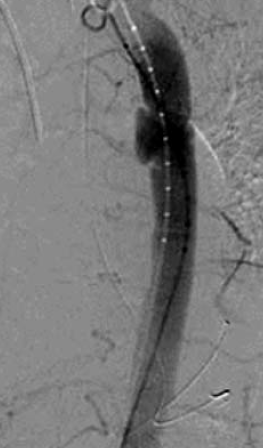

1. ábra.

Autóbalesetben sérült 26 éves ffi. DSA felvétele 3 héttel a baleset után. Az isthmicus szakaszon álaneurysma ábrázolódott.

1. 26 éves ffi autóbalesetben utasként szenvedett el mellkasi zúzódást, bordarepedést és tüdő contusiót. A kiszélesedett mediastinum és kis mennyiségű mellkasi folyadékgyülem vetette fel isthmicus tompa aortasérülés lehetőségét, amit DSA vizsgálattal igazoltunk. Hypotenziv kezelés mellett keringése stabil, a mediastinum kiszélesedése és haematologiai statusa nem változott. 3 héttel a sérülést követően bal oldali thoracotomia útján aorto-aorticus Dacron grafttal, mesterséges keringés alkalmazása nélkül, interpositiot végeztünk (1.,2.,3. ábra).